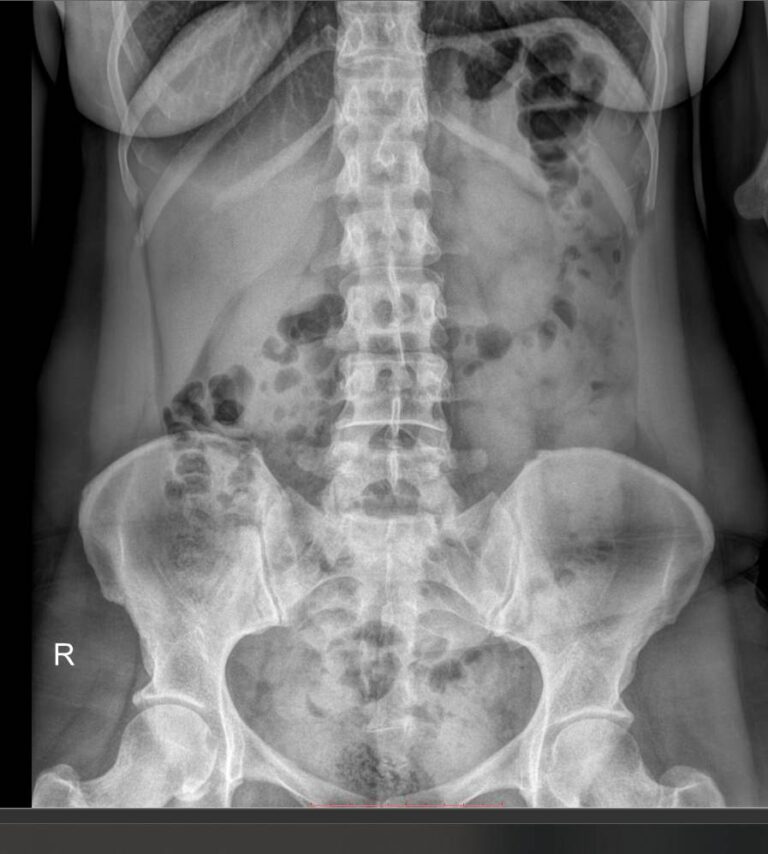

Что показывает обзорный рентген мочевыделительной системы

У здорового человека обзорный снимок покажет:

- Тени почек и мочевого пузыря;

- Мочеточники ― только при значительных изменениях;

- Нижние грудные, поясничные позвонки, ребра, тазовые кости;

- Тени поясничных мышц.

На рентгенограмме будут видны такие патологии, если они есть:

- Увеличение или уменьшение почек в размерах ― признак врожденной аномалии, воспаления и других заболеваний;

- Камни в почках и мочевом пузыре;

- Коралловидные камни в почках;

- Конкременты в желчном пузыре;

- Флеболиты ― камни вен малого таза;

- Опухоли и очаги склероза в костях малого таза;

- Обызвествленные хрящи ребер и лимфоузлы;

- Инородные тела.